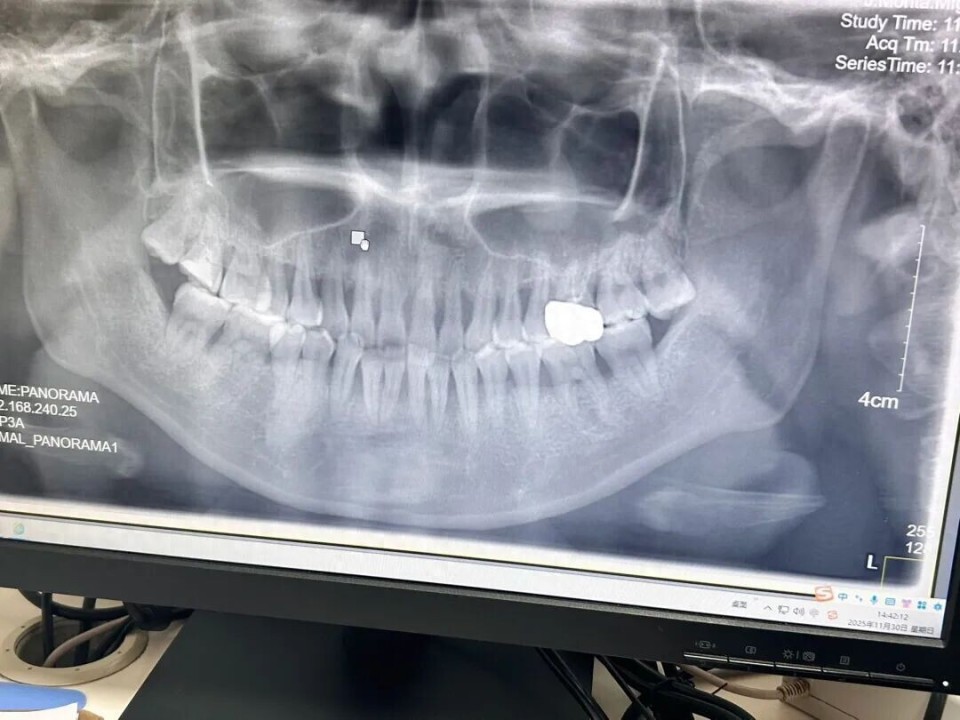

2025年11月,赵玥于武汉市一家三甲牙齿专科医院拍摄的牙片 图/受访者提供

赵玥今年27岁,她的牙周病史则能追溯到大学时期。当时,她突然发现刷牙时牙龈会出血,但对牙周病了解甚少,只是简单去医院定期洗牙。赵玥所在城市不发达,医生未提及牙周病问题,加之洗牙后出血的症状确实减轻了,以为算是好转,但其实病程并未中断。去年在武汉就医时,她已有一颗牙酸痛、轻微晃动,被确诊为重度牙周病,测量出牙周袋深度达7—10毫米。